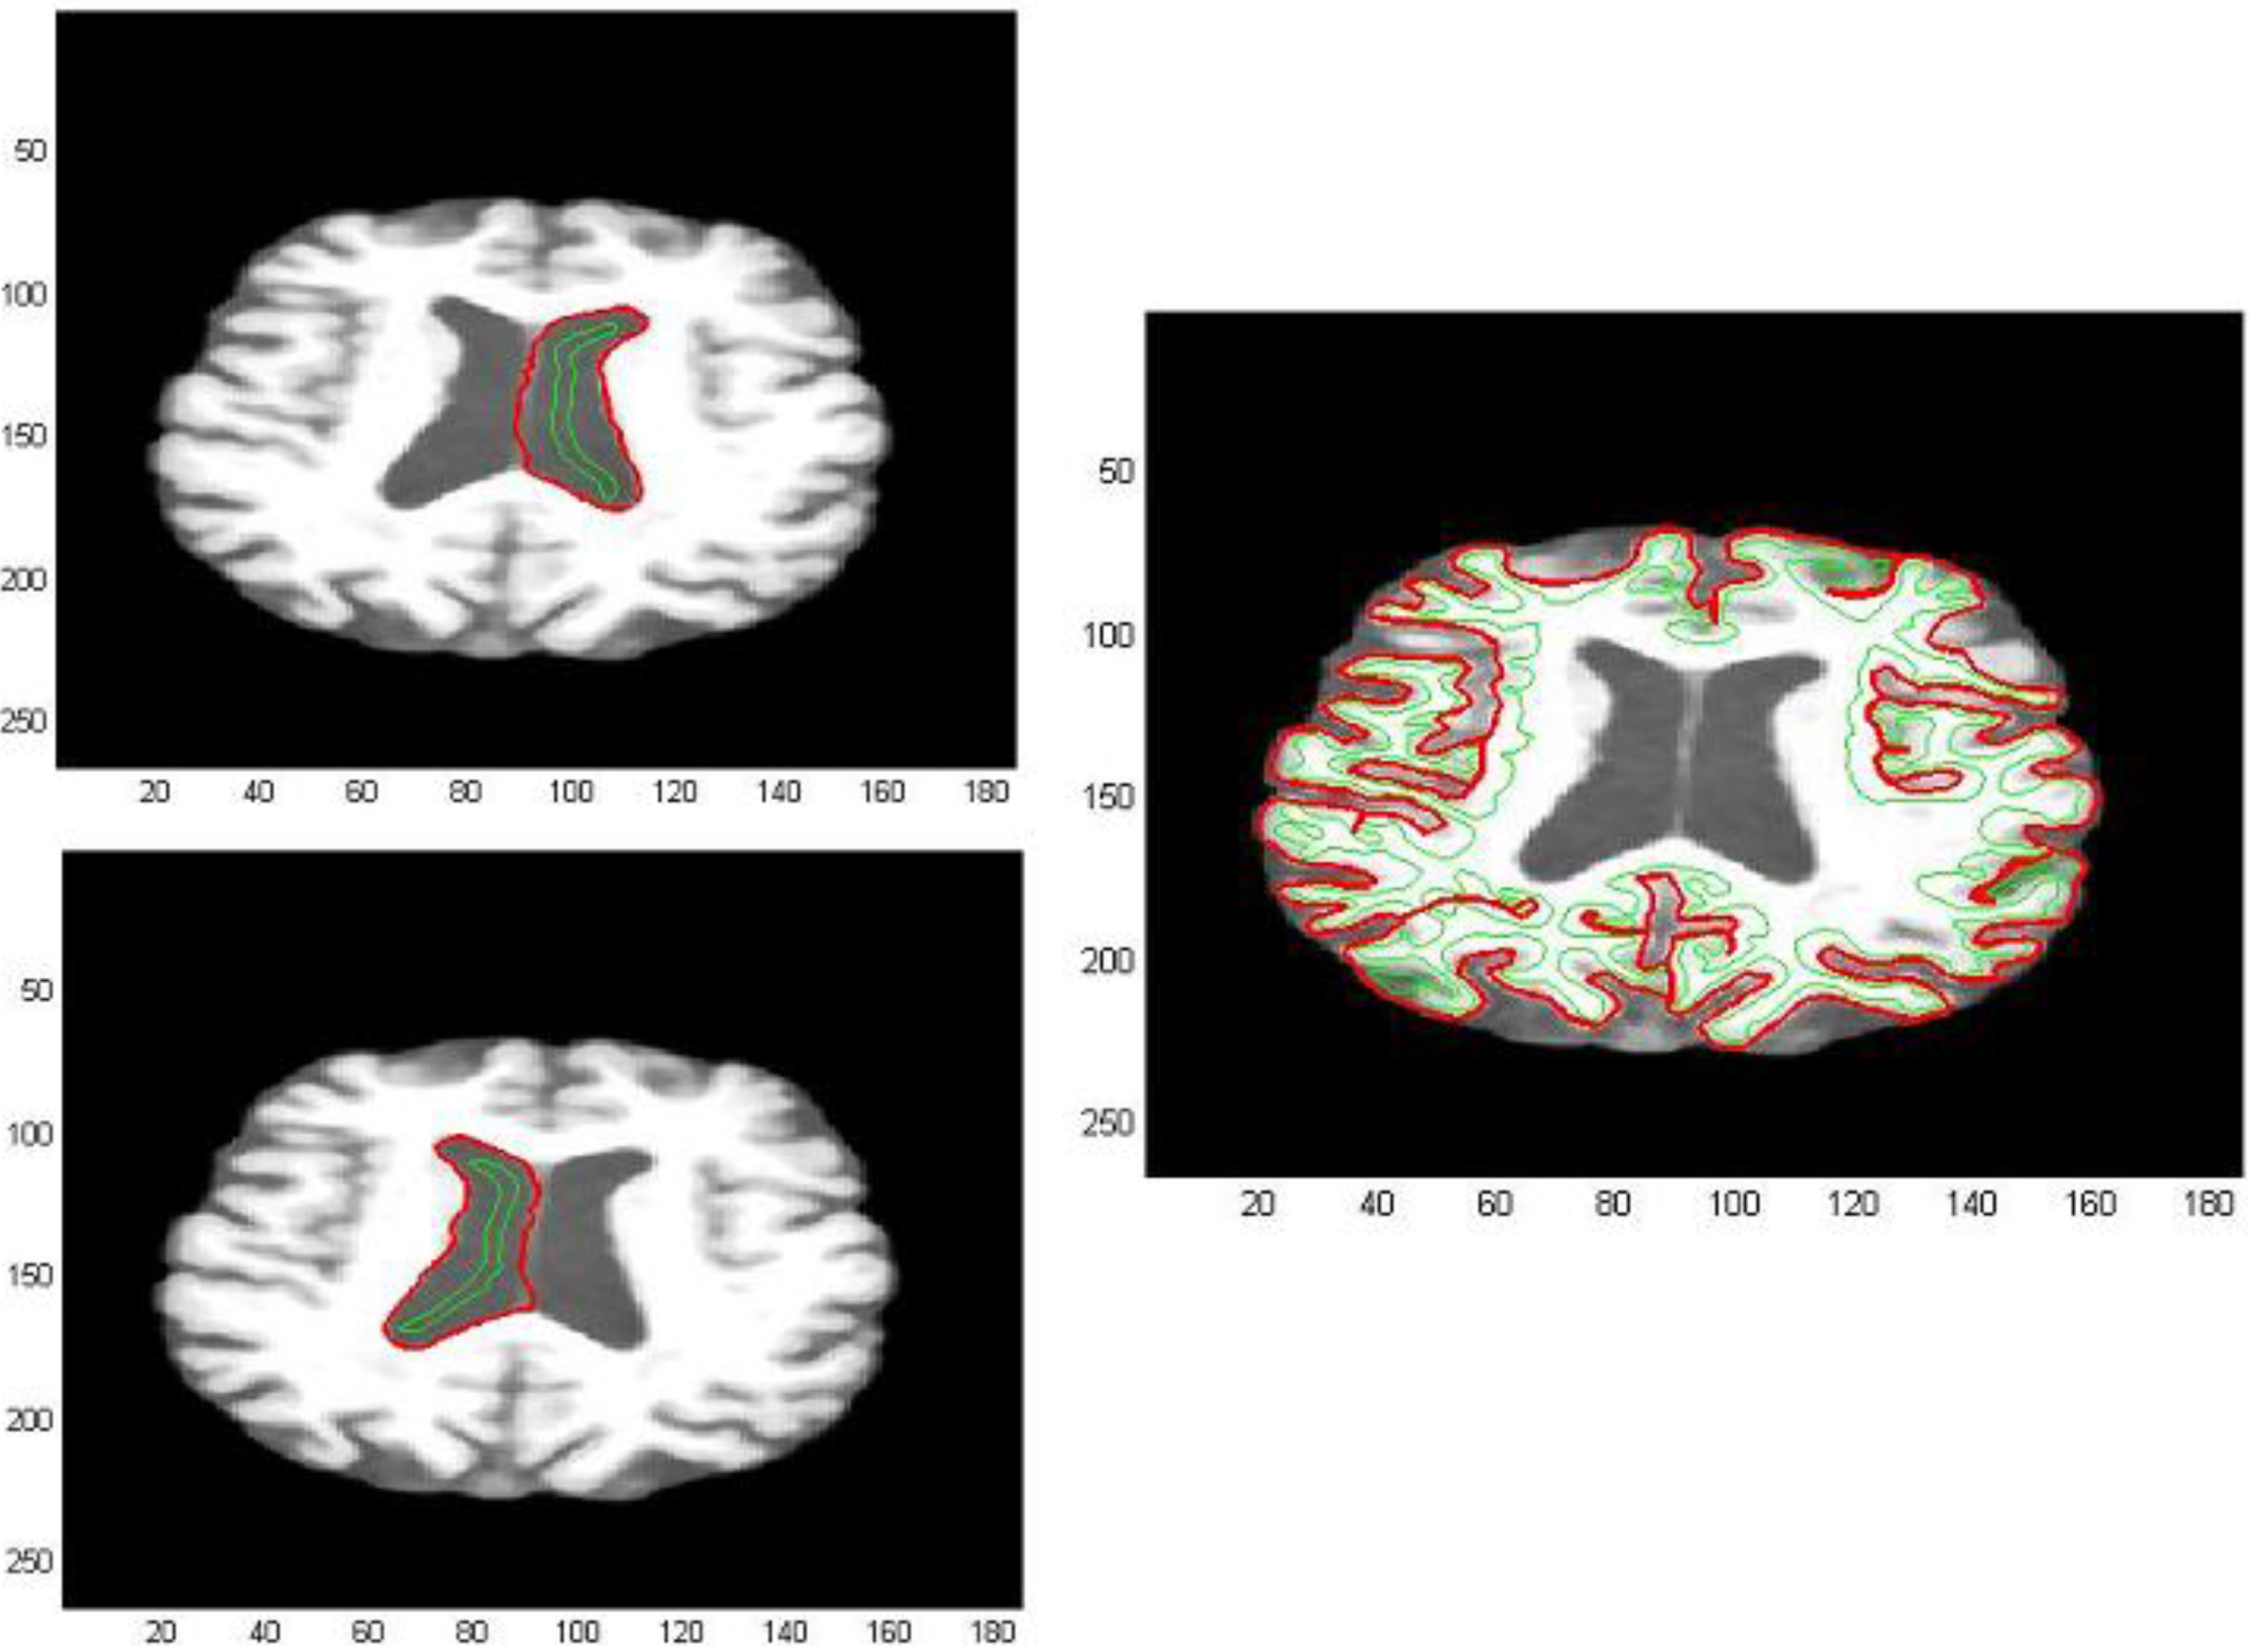

The first processed GM image (Figure 11) refers to a subject of the control group (see the first image of Figure 12). The force field has been evaluated from Equation (9) after eight iterations, the overlapping green curves represent initial contours that are automatically selected from the contour map of divergence. In Figure 13 and Figure 14 we have treated GM images derived from two patients affected by Alzheimer’s disease and they refer respectively to the second and third images which are shown in Figure 12. Once edges are detected, we produce a boundary representation of gray matter that can be used for an automatic analysis of shapes from the geometrical, metrical or morphological point of view.

Figure 11. Edge extraction with AVF force field after 8 iterations.

Algorithms 05 00636 g011

Figure 12. GM images for a subject of the control group and two patients affected by Alzheimer’s disease.

Algorithms 05 00636 g012

Figure 13. Edge extraction with AVF force field after 8 iterations.

Algorithms 05 00636 g013

Figure 14. Edge extraction with AVF force field after 8 iterations.

Algorithms 05 00636 g014

Moreover, we test the AVF method with T1-weighted MRI images of our dataset. The initial positions of the active contours are shown in green overlaid on the real image, whereas the outlines of the final contours are drawn in red. Many details of borders are captured both for gray matter and lateral ventricle profiles, whereas the interhemispheric fissure contours results are not completely retrieved, as we can see in Figure 15.

Figure 15. T1-Weighted axial image for a non-pathological subject.

Algorithms 05 00636 g015